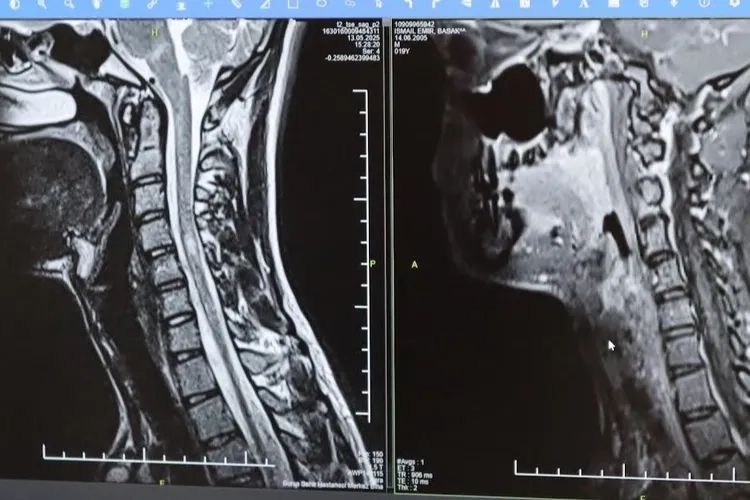

Bursa Şehir Hastanesinde görevli Nöroloji Uzmanı Prof. Dr. Özden Kamışlı, 30 Mayıs Dünya MS Günü kapsamında açıklamalarda bulundu. MS’in, bağışıklık sisteminin sinir sistemine saldırmasıyla gelişen kronik bir hastalık olduğunun bilgisini veren Prof. Dr. Kamışlı, "Dünyada yaklaşık 2.8 milyon MS hastası olduğu bilinmektedir. MS genellikle 20-40 yaş arası gençleri etkilemektedir. Bununla birlikte çocukluk döneminde ya da ileri yaşta da ortaya çıkabilmektedir. Kadınlarda görünme sıklığı erkeklere göre bir buçuk kat daha fazladır" dedi. MS hastalarının çeşitli şikâyetlerle hekimlere başvurduğunu vurgulayan Kamışlı, "Bunlar arasında görme bozukluğu, kol ve bacakta kuvvetsizlik, uyuşmalar, dengesizlik, yürüme bozukluğu, idrar problemleri veya aşırı yorgunluk ve halsizlik hali bulunmaktadır. MS ataklarla seyredebilir ve genellikle en sık görülen formu budur. Birdenbire bir şikâyet ortaya çıkar ve zamanla azalır veya kaybolur. Bir de progresif dediğimiz ilerleyici formu vardır. Bu ilerleyici formda hastalık yavaş yavaş ilerlemektedir. MS her hastada farklı seyreder. Bu nedenle tek tip bir MS hastalığından bahsetmek mümkün değil" şeklinde konuştu.

TEDAVİDE GELİŞME KAYDEDİLDİ Hastalığın tanısını ne kadar erken konulursa ve tedaviye ne erken başlanırsa; hastaların günlük hayatta aktif ve üretken bir şekilde devam etmelerinin o kadar kolaylaştığına dikkat çeken Kamışlı, "Günümüzde MS'le ilgili çok fazla gelişme oldu ve tedavi seçenekleri arttı. MS merkezlerinde bu tedavi seçeneklerine ulaşmaları mümkün. Hastalarımız için doğru tanı, düzenli takip ve uygun tedavi oldukça önem teşkil etmektedir" diye konuştu.